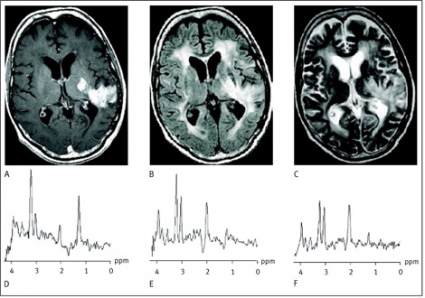

Avkapslade bakteriella hjärnabscesser kan differentialdiagnostiskt vara svåra att skilja från cystiska eller nekrotiska primära hjärntumörer eller metastaser såväl som från opportunistiska eller parasitära infektioner. MR-spektrumet av den cystiska komponenten i en pyogen abscess återspeglar bakteriernas metabola aktivitet och har ett karakteristiskt utseende [5]. Avsaknaden av kolin, kreatin och N-acetylaspartat, ackumulationen av laktat och alifatiska CH3- och CH2-grupper samt förekomsten av metaboliter som normalt inte ses i ett humant hjärnvävnadsspektrum (acetat, succinat och alanin) ger spektrumet dess karakteristiska utseende (Figur 2).

Vid avsaknad av de sistnämnda abscesspecifika metaboliterna återstår differentialdiagnostiskt även den sterila abscessen. Under antibiotikabehandling försvinner dessa metaboliter. Ett sådant spektrum kan representera en steril abscess likaväl som någon annan form av cystisk nekrotisk hjärnlesion (Figur 2 C) [6, 7]. En analys av cystans omgivande vävnad kan i dessa fall ge ytterligare information om lesionens genes.